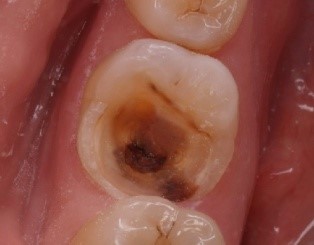

Одна из форм носит название серозно-гнойный пульпит. Его часто называют еще очаговым. Это начальная стадия заболевания. Бактерии попадают в стерильную пульповую камеру. Иммунная система реагирует на такое вторжение серозной жидкостью, которая начинает накапливаться в полости зуба. На этом этапе больной отлично понимает, какой зуб его беспокоит.

В ней отмечаются жалобы больного, указывается анамнез, то есть история зуба. Врач обязательно отметит: подвергался ли он раньше лечению, есть ли на нем пломба. Также в историю болезни записываются результаты осмотра. Обычно обнаруживается кариозная полость. Зуб имеет белесоватый налет. Пальпация не вызывает болезненных ощущений.